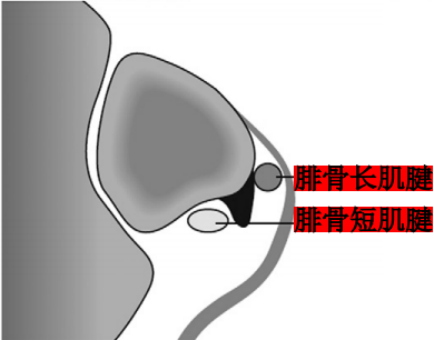

Ecket和Davis根据73例手术患者的术中观察发现并无腓骨上支持带的撕裂,他们将患者分为3型:

I型:最常见(51%),腓骨上支持带(SPR)和骨膜仍保持联系,骨膜从外踝上撕脱,腓骨肌腱滑向前方使骨膜和外踝分离。

Ⅱ型:(33%)纤维软骨脊连同腓骨上支持带(SPR)一起和外踝分离,腓骨肌腱向前脱位。

Ⅲ型:(16%)纤维软骨脊连同部分外踝骨质和腓骨上支持带(SPR)一起与外踝分离,肌腱脱位至骨折块下方。

IV型:Oden1987年在此基础上外,还有少见的第IV型,表现为腓骨上支持带(SPR)的完全撕脱或断裂,并且肌腱移位于支持带的外表面。

Raikin等学者提出将腓骨沟内腱鞘内半脱位不伴有腓骨上支持带损伤划为腓骨脱位的亚系。这些腱鞘内半脱位共有两型:

A型:腓骨肌腱无撕裂,肌腱暂时换位;

B型:腓骨短肌存在纵向撕裂,腓骨长肌腱自撕裂处半脱位。